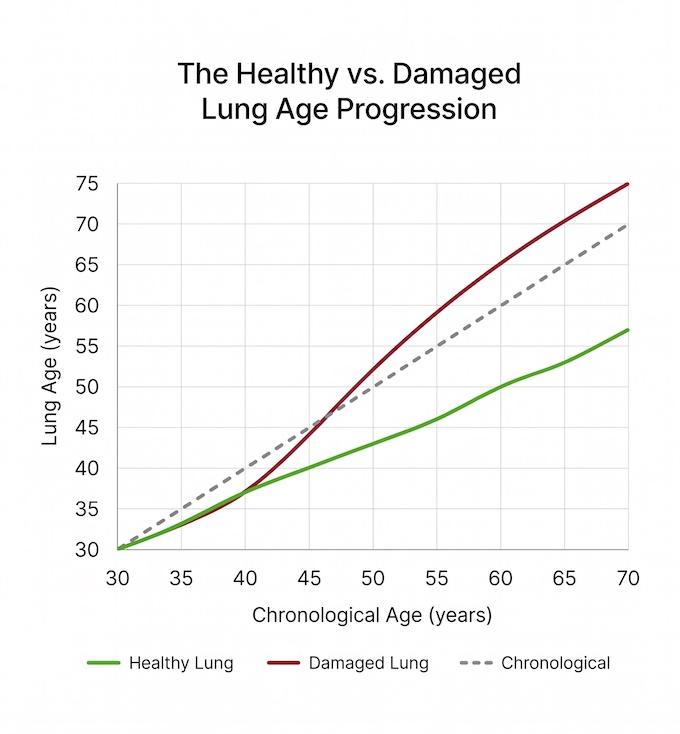

The Lung Age Problem That Changes Everything

Your lungs have a built-in clearing system. When it breaks down, your lung age starts pulling years ahead of your real age — silently, and without warning.

Note: Over time, smoking, daily pollution, tyre particle exposure, chronic illness, or long COVID damage this system — and your lung age starts aging faster than your body

Your lung age accelerates ahead of your real age

48

(Chronological age)

- lung age gap -

64

(Actual lung age)

A 48-year-old with 15 years of untreated airway buildup can have the lung function of a 64-year-old. Not from one catastrophic event — from slow, silent accumulation that felt manageable the whole time.